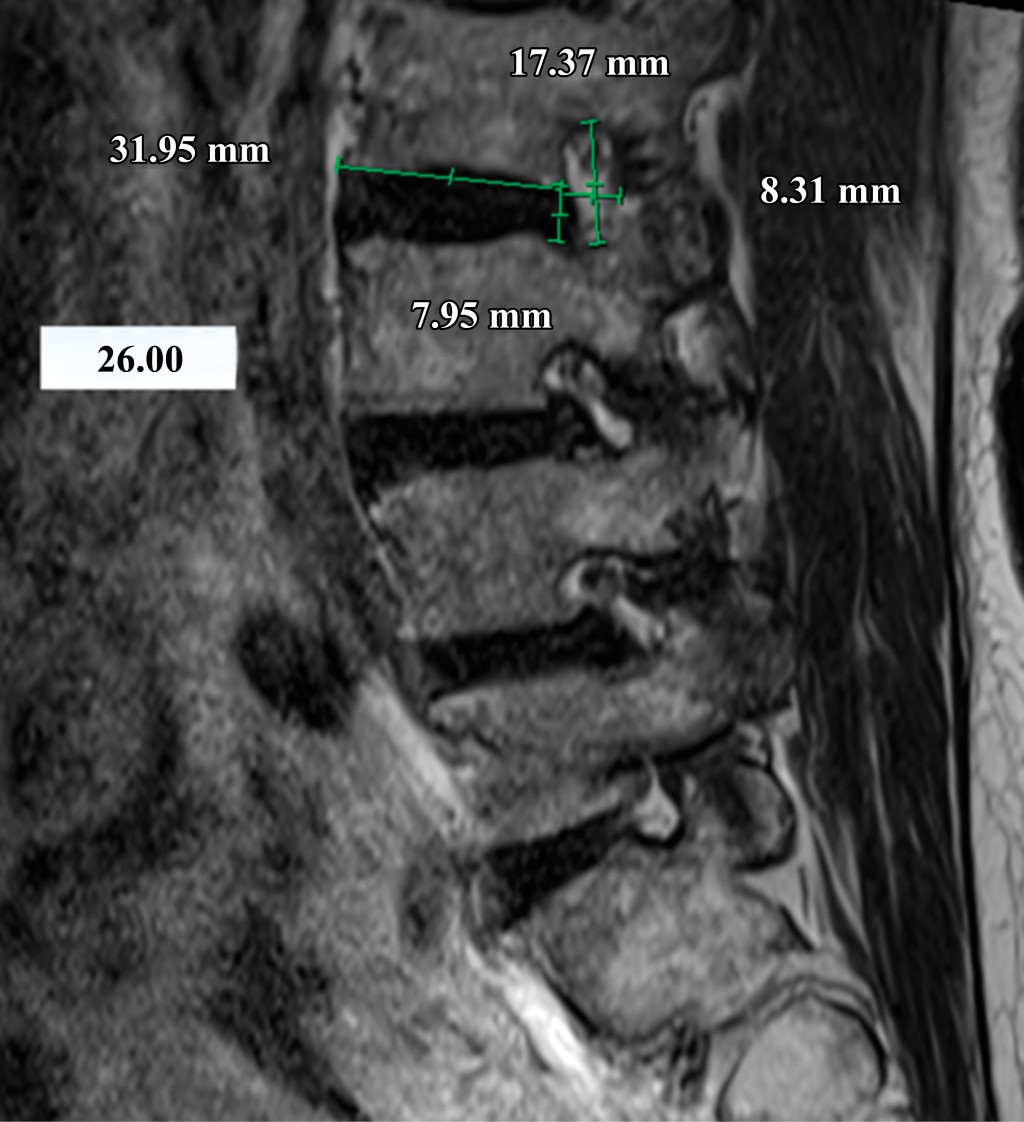

Introducción: la estenosis foraminal lumbar se define como el estrechamiento del canal lateral por donde sale la raíz nerviosa del canal espinal en la columna lumbar, ocurre de 8-11% en pacientes mayores de 40 años. El fallo en la detección y descompresión del foramen representa 60% de las causas de cirugía lumbar fallida. Este estudio tuvo como objetivo generar un índice que evalúa el grado de estrechez foraminal y así apoyar la toma de decisiones para una descompresión foraminal directa o indirecta. Material y métodos: se realizó un estudio transversal, donde se incluyeron 49 pacientes a los cuales se les midieron los cinco forámenes lumbares con rayos X y resonancia magnética simple. Estas mediciones incluyeron principalmente el ancho foraminal y la plataforma vertebral inferior del cuerpo vertebral superior y se correlacionaron para formar un índice ancho foraminal/plataforma vertebral inferior. Resultados: el índice ancho foraminal/plataforma vertebral inferior < 10% tiene un OR de 3.07 en la radiografía lateral, un OR de 3.59 en la radiografía en flexión y un OR de 4.01 en la radiografía en extensión. En la resonancia magnética se obtuvo un OR de 0.195 para los forámenes izquierdos y un OR de 3.07 para los forámenes derechos. Conclusión: este estudio abre el camino para una mayor exploración de los resultados clínicos preoperatorios y postoperatorios en diversos métodos de descompresión quirúrgica guiados por el índice FW/LE. Para mejorar la toma de decisiones, se recomienda realizar una investigación que compare los hallazgos clínicos preoperatorios y postoperatorios en pacientes individuales, teniendo en cuenta sus mediciones del índice FW/LE.

Figura 2